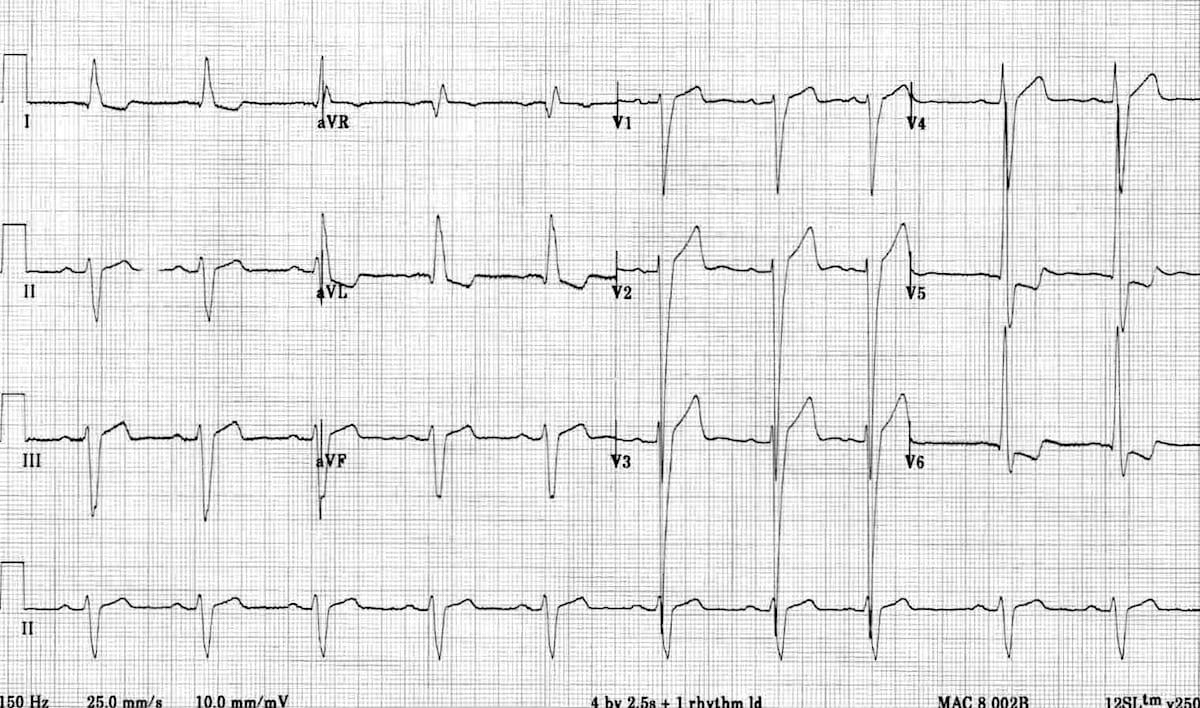

This is an ECG of LBBB. First, note the widened QRS complex across all leads. Second, a deep S wave is seen in V1 along with a dominant R wave in V6. Third, discordant changes are best seen in V1, where there is ST elevation and upright T wave while the QRS is -ve (dominant S wave).